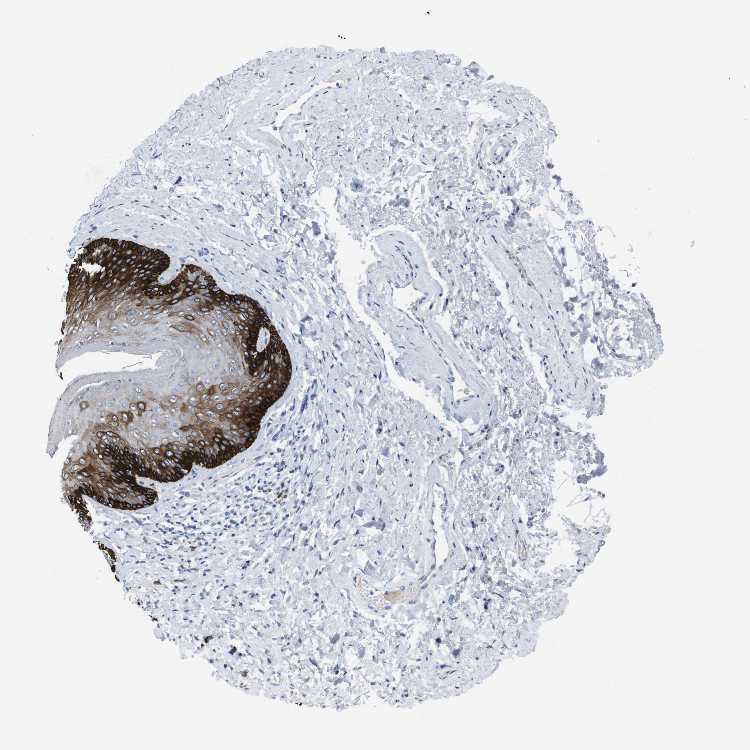

SKIN 1 - Antibody stainingi

Antibody staining in the annotated cell types in the current human tissue is reported as not detected, low, medium, or high, based on conventional immunohistochemistry profiling in selected tissues. This score is based on the combination of the staining intensity and fraction of stained cells.

Each image is clickable and will lead to virtual microscopy that enables deeper exploration of all samples and also displays staining intensity scores, fraction scores and subcellular localization as well as patient and tissue information for each sample.

Antibody CAB013093

Langerhans High

Fibroblasts Not detected

Keratinocytes Medium

Melanocytes High